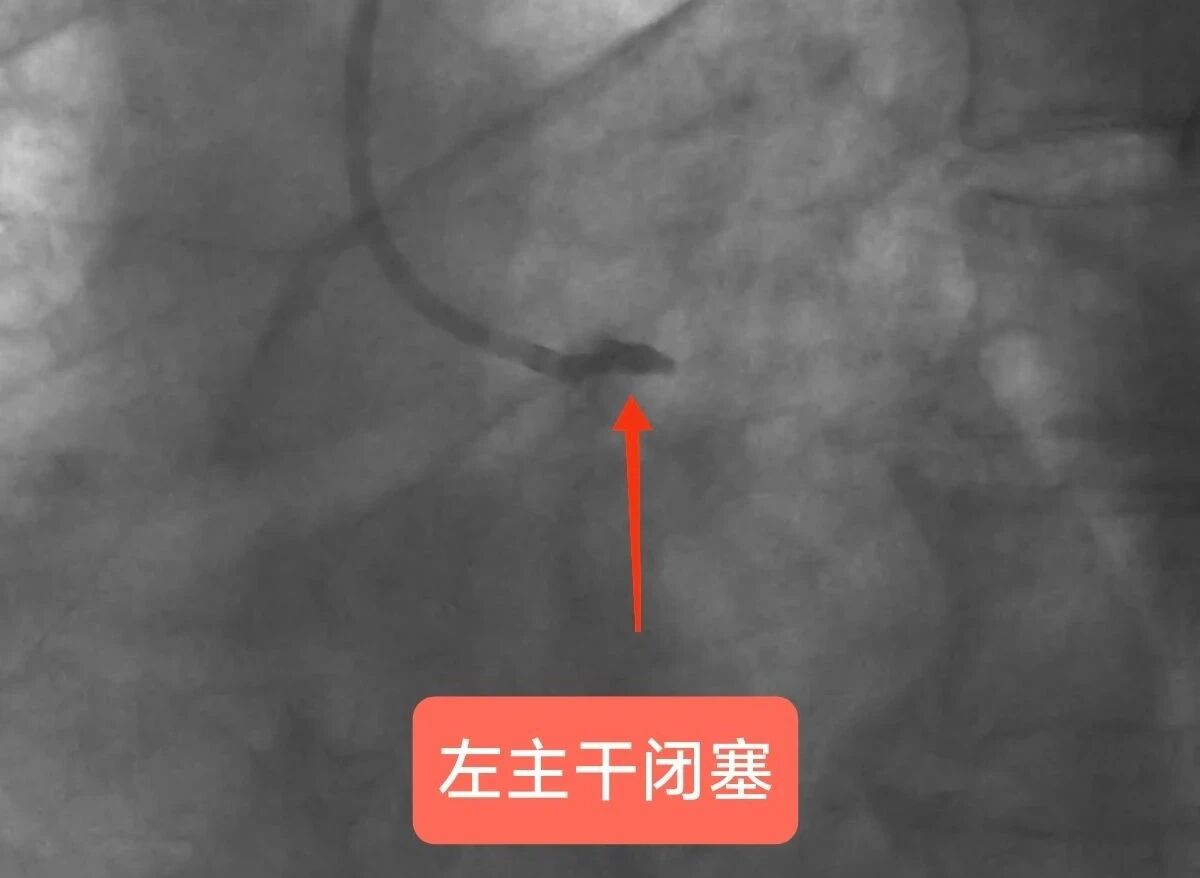

冠脉造影显示患者左主干血管闭塞

玉溪市人民医院派驻心内科专家李驹、玉溪市中山医院心内科副主任李国辉团队紧急启动手术。术中,李驹指导实施急诊PCI手术,迅速打通钟先生堵塞血管,并植入支架及时恢复心脏血液供应。由于钟先生常规穿刺部位的血管条件不佳,李驹便从大腿根部血管(股动脉)用超声引导插入导管进行冠脉造影,造影发现钟先生心脏核心血管——左主干急性完全堵塞,其他分支血管也堵塞严重,心脏几乎得不到供血,随时可能心跳停止。